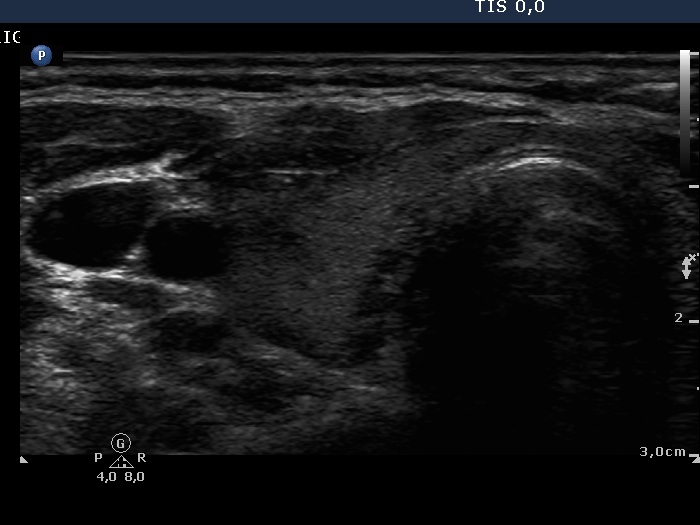

First examination (1st row of images)

Clinical data: A 29-year-old woman requested a second opinion. She was treated for Graves' disease for 2 months. The TSAb was initially 8.9 U/L, the FT4 was 54.2 pM/l. She get 30 mg methimazole therapy. Her complaints have already decreased.

Palpation: no abnormality.

Results of blood test: hyperthyroidism - TSH undetectable, FT4 29.2 pM/L, FT3 8.91 pM/L.

Ultrasonography: The thyroid was minimally enlarged and moderately hypoechogenic. The vascularization was a bit increased.

The dose of methimazole was reduced to daily 15 mg.